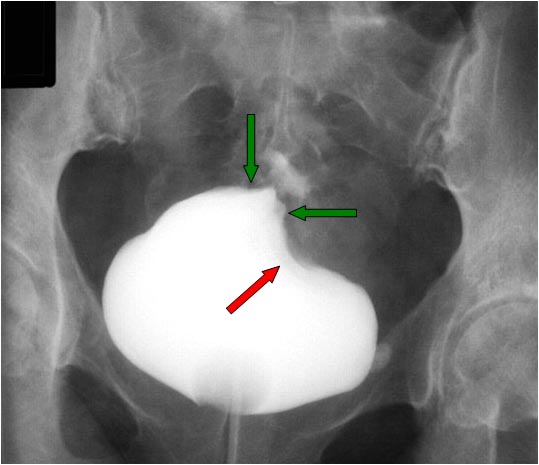

Signos de fístula colovesical en la cistografía. El extremo vesical de la fístula se asocia con la imagen de una deformidad biconvexa triangular (flechas verdes) que acaba en un punto bien definido, como si se insinuase el contraste en la boca de la fístula. De hecho puede verse contraste fuera de la vesícula, por encima de ese ángulo que forma el borde superior vesical.

En nombre del Signo de la colmena se debe a que la vejiga queda deformada adoptando una forma que recuerda a la celda de una colmena.

El Signo del heraldo es un signo temprano visible en el borde superior de la vejiga, en forma de semiluna. Es un hallazgo descrito en 1961 del que no hemos encontrado imágenes. Hemos marcado con flecha roja el borde semilunar de la vejiga, pero no sabemos si se trata en realidad de este hallazgo.